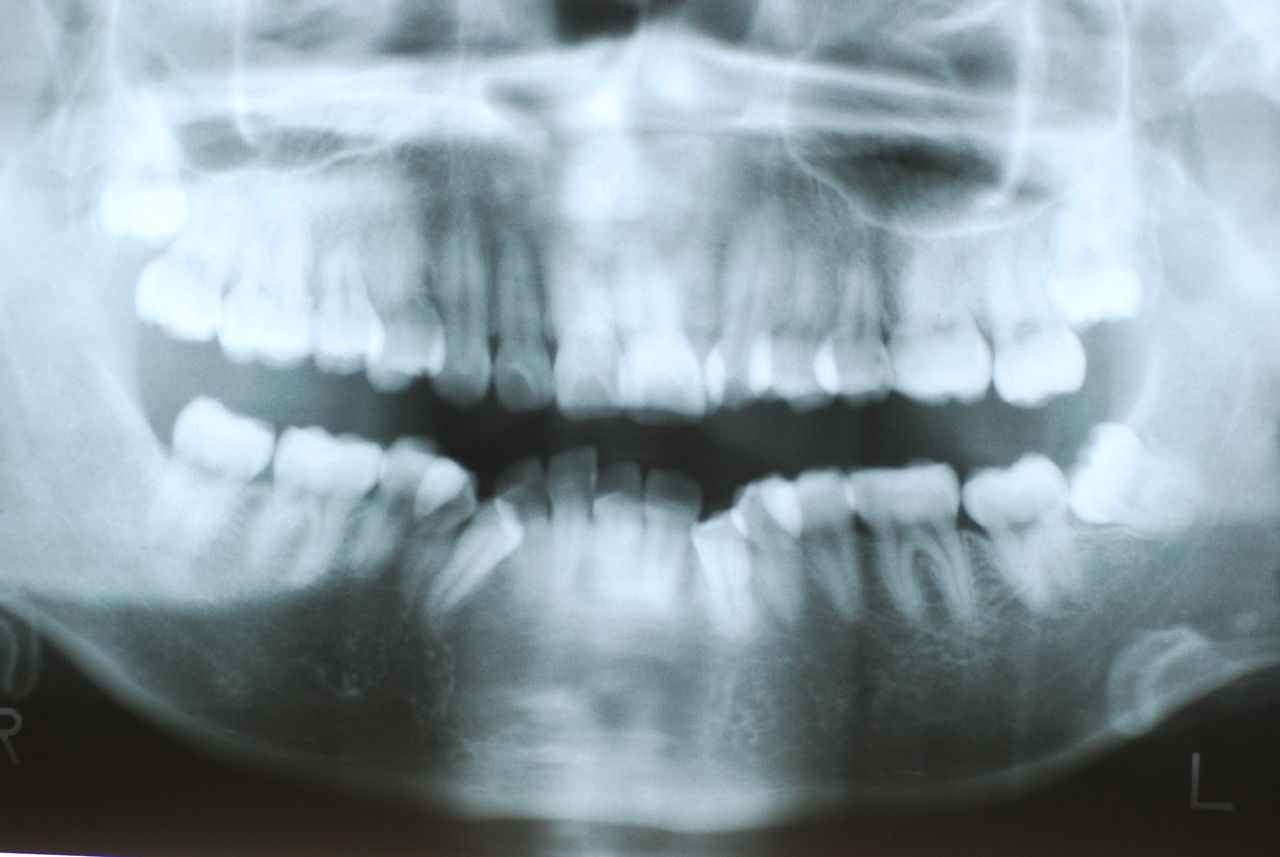

上の総義歯はまっったくはずれませんでした。下顎の入れ歯では若干痛みが出そうなので噛み合わせの調整をしています。口腔内では時間がかかりすぎるので器械に付けて調整しています。

下顎が右にシフトしているので噛み合わせはとても慎重にしました。下の方が頬側にないと安定せず噛めないのです。

左側の噛み合わせはまともにできます。